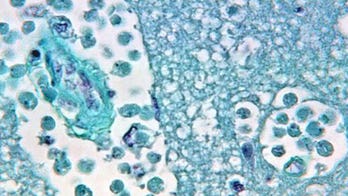

Flesh-eating bacteria - Page 6